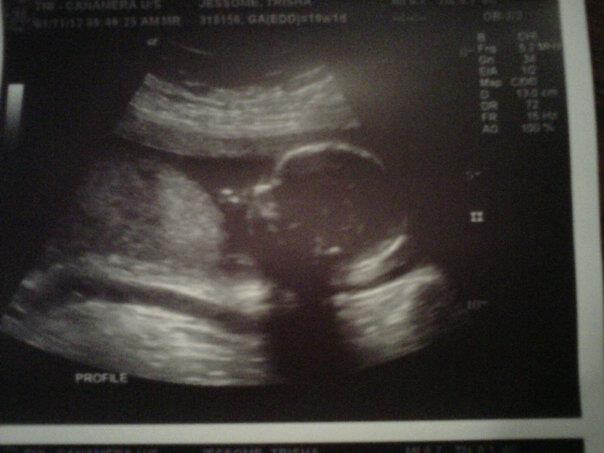

My friend told me about this site and that you might be able to help me figure out the sex of my baby. I am 19 weeks and we had our ultrasound Attachment 5858

We need a nub shot to go off of though. Sweet baby! :)

Skull theory guesses?

I never got a 12 week ultrasound. My friend said you might be able to tell by the skull. If not that is fine I will just have to wait till March :)

Id say girl skull, its just a guess though.

to tell gender nub shot or potty shots are required but for fun i guess girl its just guess

You all guess right. Got a sweet baby girl :)